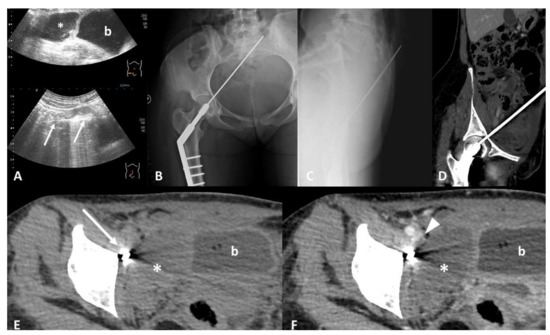

3. Device Integrity and Migration

4.2. Parenchymal/Tissue Injury